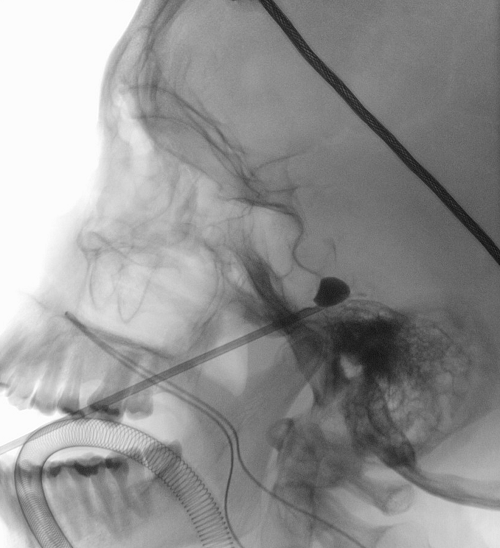

In those cases where microvascular decompression surgery is not indicated, there are other less invasive techniques (percutaneous). This is done by placing a needle in the trigeminal nerve and controlled injury of the fibers that transmit the pain. In the indicated cases, the improvement is almost immediate and the results are also satisfactory in the long term.